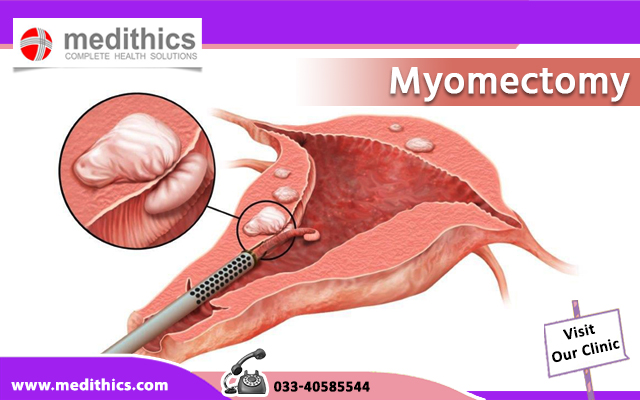

Современные методы лапаротомии и миомэктомии